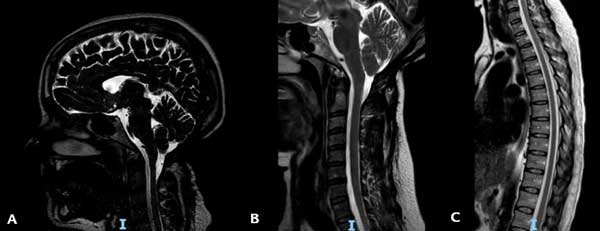

La RM de control realizada en octubre 2023 mostró un ascenso de las amígdalas cerebelosas y una resolución completa de la siringomielia (Figura 5). Actualmente sigue bajo control y solo persisten una leve hipoestesia en la mano izquierda y parestesias en la región subescapular izquierda.

Figura 5. RM ponderada en T2 en la que se observa: A) El ascenso amigdalino. B) La resolución de la siringomielia cervical. C) La resolución de la siringomielia torácica.